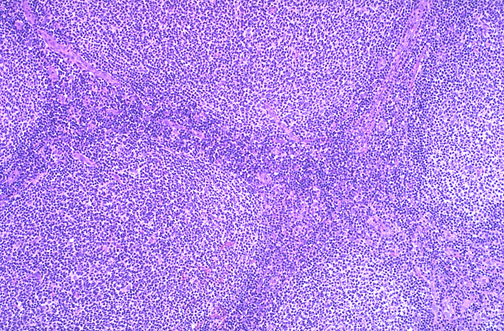

Image 2.2

At medium power, the follicles in this lymph node are seen to be crowded.